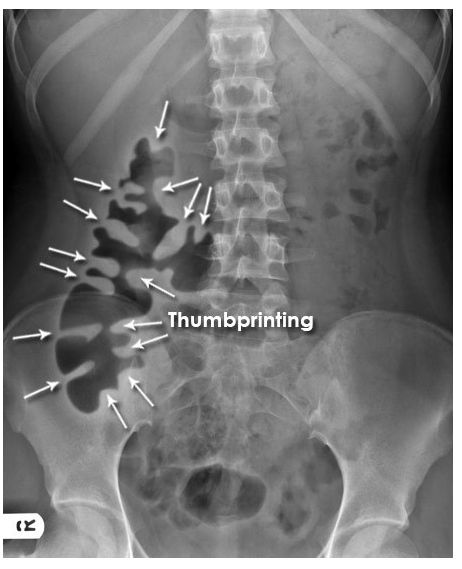

Q

What sign does this AXR show? [1]

What pathology does this indicate? [1]

A

Mucosal thickening - ‘thumbprinting’

This patient presented with an exacerbation of symptoms of ulcerative colitis.